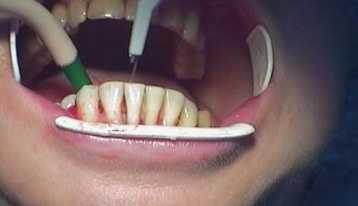

Вторым этапом становится профессиональная чистка зубов, которая необходима для устранения любых рисков развития инфекции или воспаления. Удаление налета также является этапом терапии, поскольку первопричиной расшатывания зубов могут быть твердые отложения на зубах.

Шинирование с помощью стекловолокна осуществляется в стоматологическом кабинете за один прием. Пациенту проводят местное обезболивание. Вдоль подвижных зубов, на внутренней стороне ряда на глубину 0,5 мм, проделывается бороздка для стекловолоконной нити, которая после укладки закрывается светоотверждаемым пломбировочным материалом. Свет превращает в балку композит со стекловолоконной нитью, благодаря которой зубы сцепливаются неподвижно вместе. Ответственный пациент, внимательно ухаживающий за полостью рта и следующий абсолютно всем советам стоматолога, может рассчитывать на 3-летний срок службы стекловолоконной шины. При этом ему нужно будет раз в год приходить к своему стоматологу для полировки конструкции. Не стоит шинировать передние зубы, если отсутствуют задние. Конструкция может сломаться из-за избыточной жевательной нагрузки на шинированный зубной ряд. Поэтому перед процедурой стекловолоконного шинирования необходимо навести порядок с прикусом и запротезировать недостающие зубные единицы.

- Выполнение на задней поверхности зубного ряда ровной борозды (глубина 0,5 мм).

Весь процесс установки не занимает больше двух часов. Сначала нужно выполнить очистку эмали, потом создать на ней небольшую борозду. После этого лента из стекловолокна фиксируется на композитные материалы. После того как конструкция отшлифована, врач убедился, что пациенту ничего не мешает, работа считается завершенной.